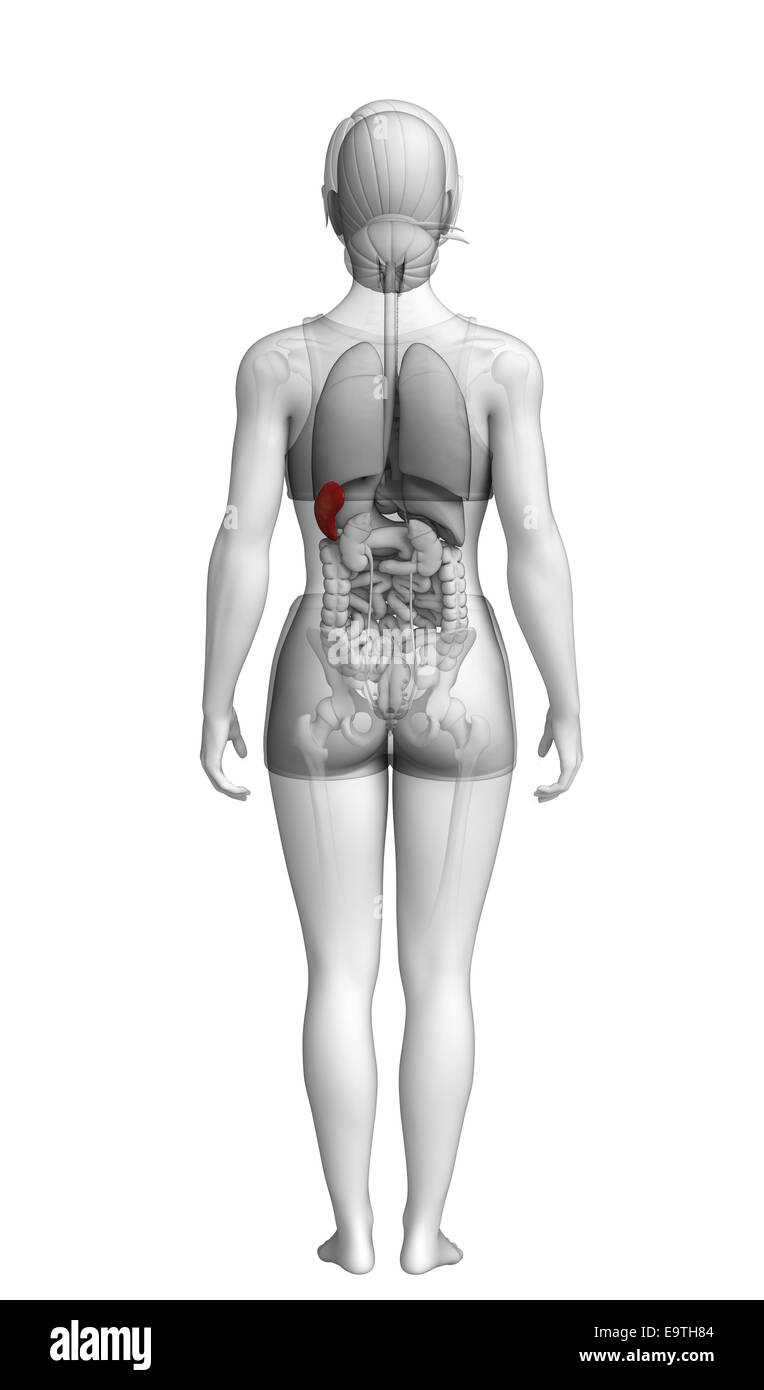

Illustration de l'anatomie de la rate femelle Banque D'Imageshttps://www.alamyimages.fr/image-license-details/?v=1https://www.alamyimages.fr/photo-image-illustration-de-l-anatomie-de-la-rate-femelle-74913780.html

Illustration de l'anatomie de la rate femelle Banque D'Imageshttps://www.alamyimages.fr/image-license-details/?v=1https://www.alamyimages.fr/photo-image-illustration-de-l-anatomie-de-la-rate-femelle-74913780.htmlRFE9TH84–Illustration de l'anatomie de la rate femelle